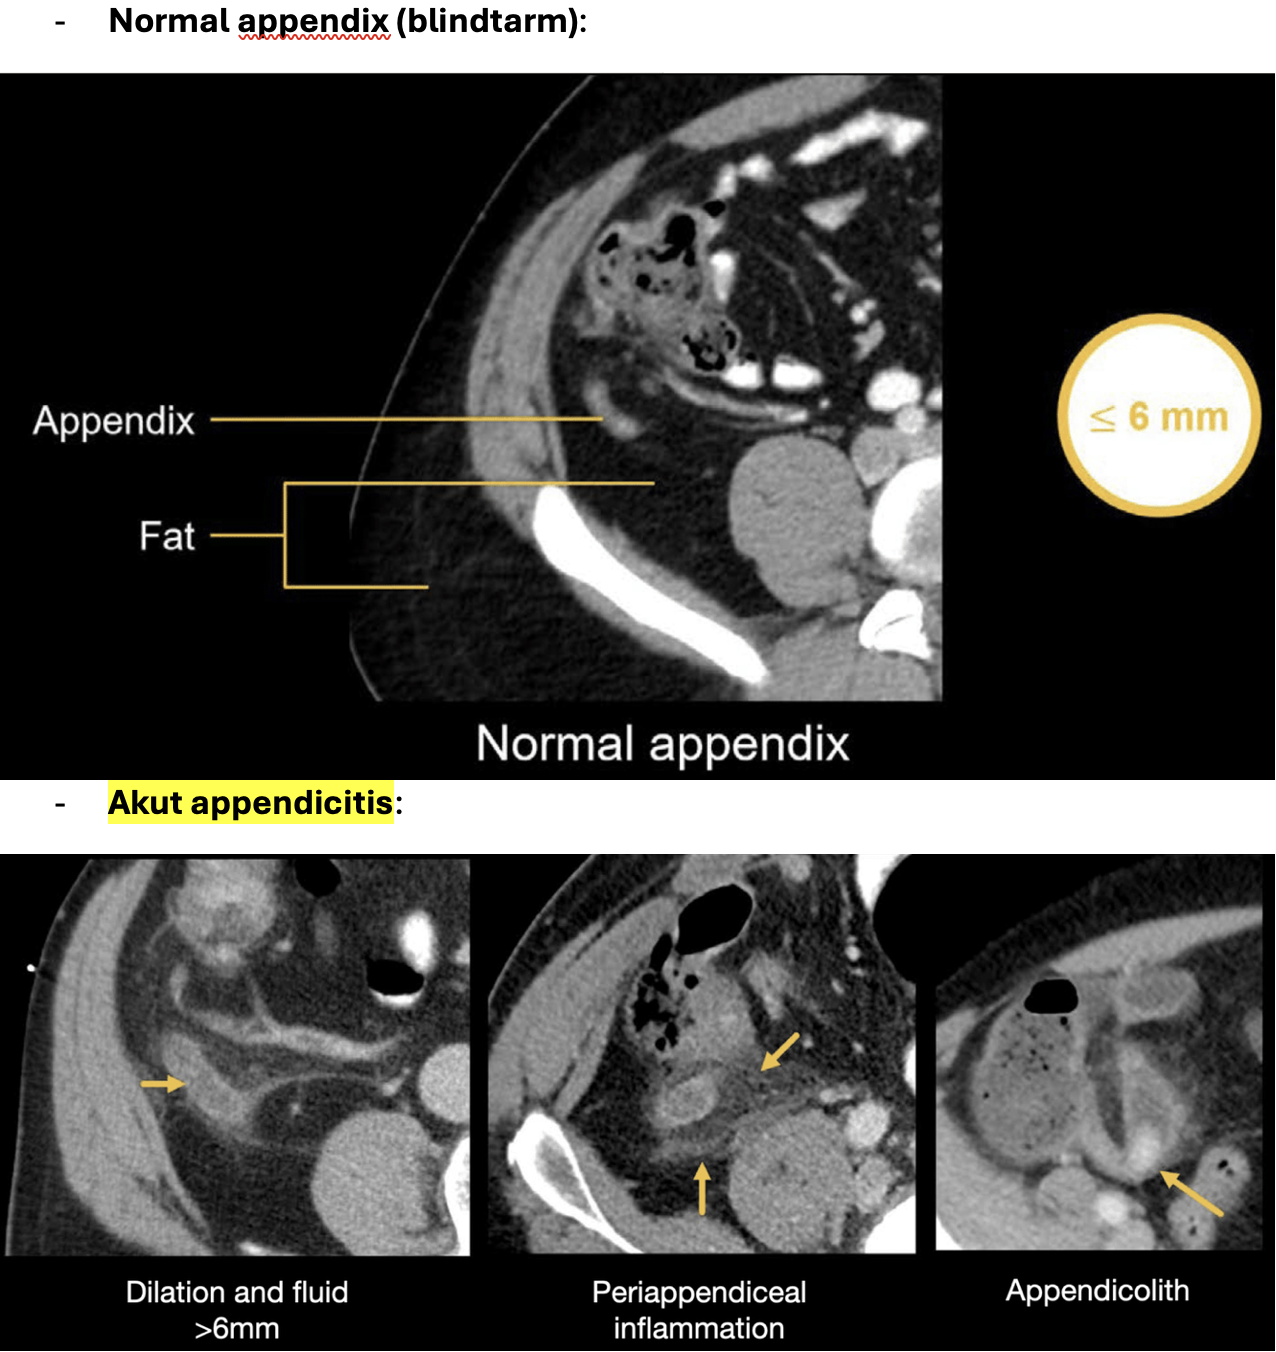

Akut appendicitis:

8

Q

Diagnose?

A

Akut appendicitis